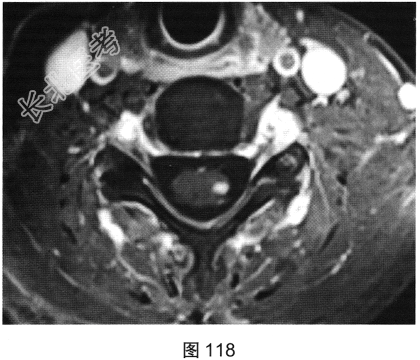

- 多项选择题2.[提示]患者行脊柱MRI检查,如图115~图120所示。患者MRI检查可见哪些阳性影像学表现( )

A、T2WI示颈髓和胸髓病灶呈高信号

B、增强扫描颈髓病灶多发斑片状强化

C、横断面增强扫描脊髓侧索病灶强化

F、T1WI示颈髓病灶呈等信号